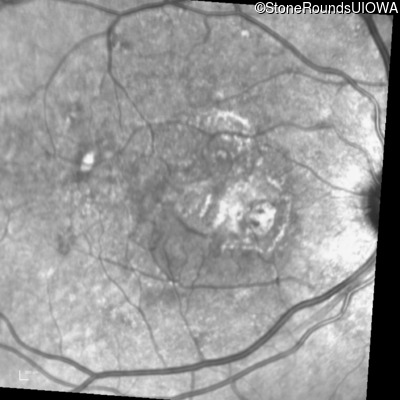

Fluorescein Angiography - Right - 20/250

Exemplar